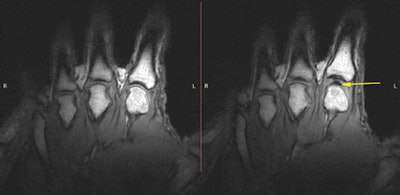

Kawchuk's group used a Magnetom Sonata (Siemens Healthcare) 1.5-tesla MRI system with a finger coil provided by the company. For the study, the single participant lay prone with his hand attached to the radiofrequency coil, which was then threaded through the magnet. The team took static images of the subject's 10 metacarpophalangeal (MCP) joints before and after taking a cine MR acquisition, during which force was increasingly applied manually through the coil until the study participant indicated that the joint had cracked (PLOS One, April 15, 2015).

radiofrequency coil (above left). The participant's hand within the imaging magnet (above right). All images courtesy of PLOS One.

All 10 of the subject's MCP joints cracked. The static MR images showed normal MCP joints without any gas bubbles before cracking; after cracking, static imaging showed a dark intra-articular space, according to Kawchuk's team.